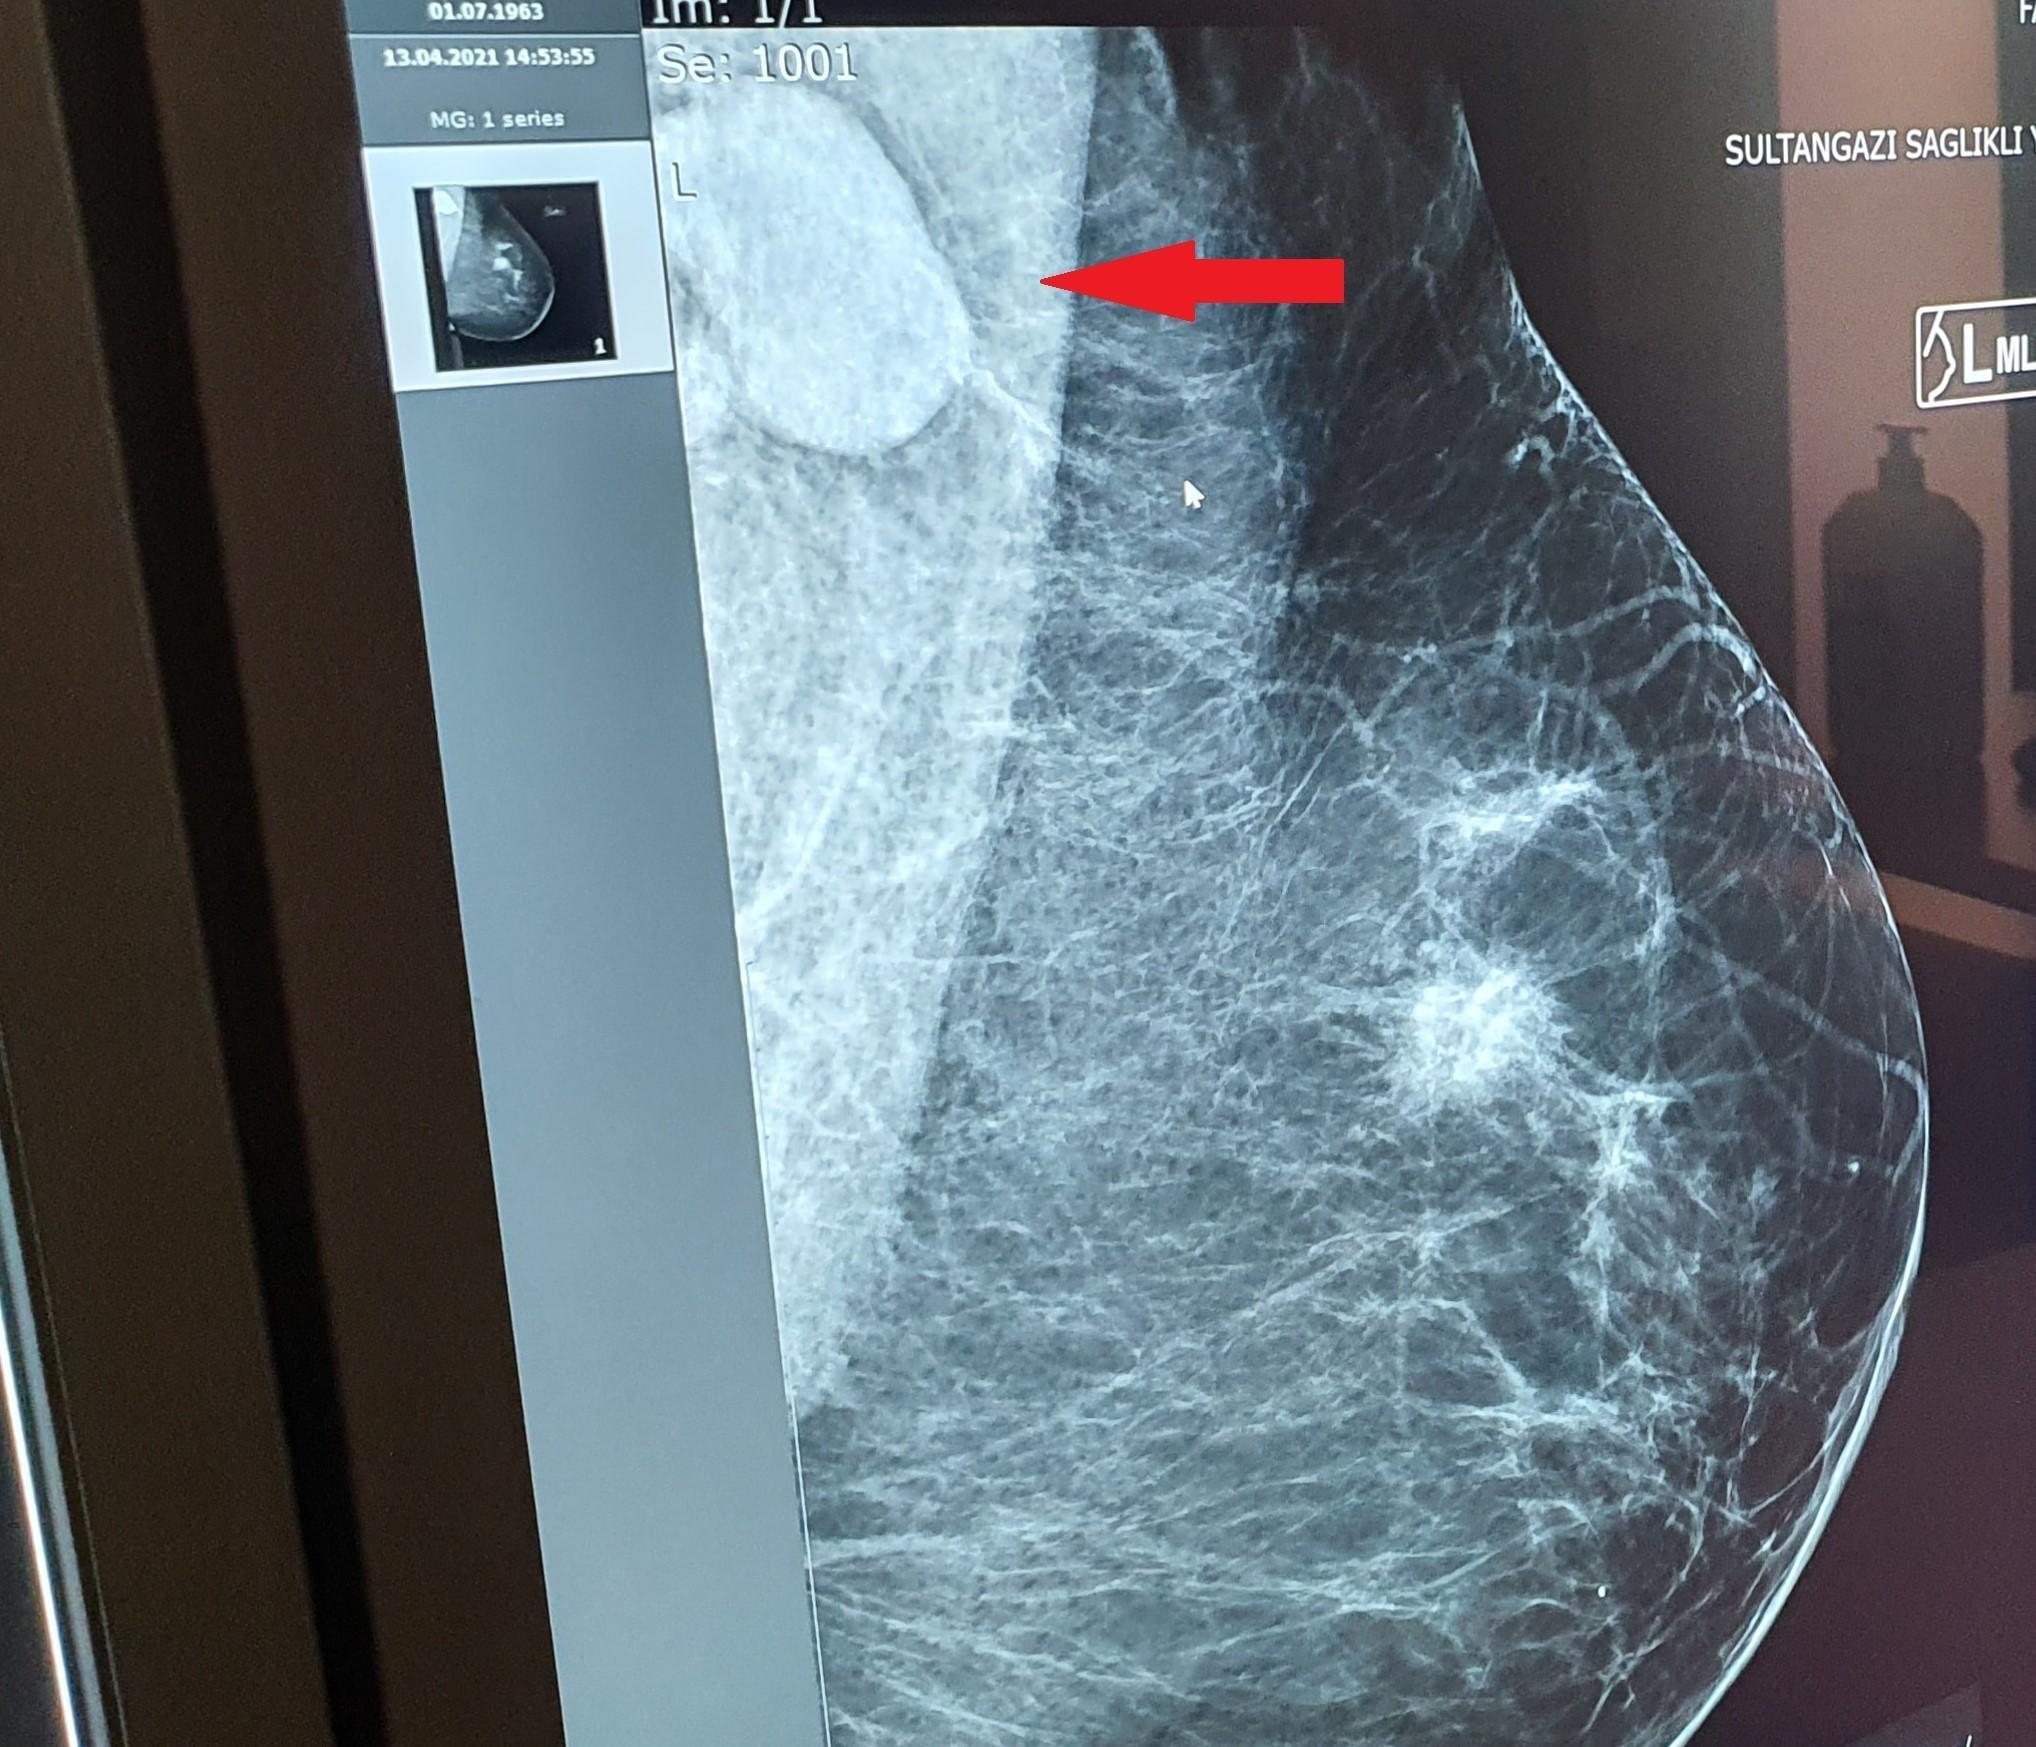

Meme kanserinin en önemli belirtilerinden biri olan koltuk altı lenf bezlerindeki tutulumlar, vücudun bağışıklık yanıtı nedeniyle bazen enfeksiyon ya da aşıdan sonra da gelişebiliyor. Ancak aynı dönemde mamografi taramasına giden kadınlarda, özellikle tek taraflı lenf tutulumu, meme kanseriyle karışabiliyor.

Enfeksiyonlarda genellikle çift taraflı tutulum olduğu için, çoğu zaman meme kanserinden kolaylıkla ayırt edilebildiğini belirten Haseki Eğitim ve Araştırma Hastanesi Radyoloji Kliniği İdari Sorumlusu Yrd. Doç. Dr. Türkan İkizceli, memede kitle olmasa da tek taraflı lenf tutulumlarında kanser şüphesinin akla daha çok geldiğini belirterek, “Kovid aşılamalarının artmasıyla beraber, mamografi taramasına gelen kadınlarda tek taraflı lenf tutulumlarına daha sık rastlamaya başladık. Özellikle aşı yaş takviminin düşmesiyle beraber, bu tip olgulara çok daha fazla rastlayacağımızı düşünüyoruz. Hastaların gereksiz yere biyopsi gibi ileri girişimsel tetkiklere yönlendirilmemesi için, radyologlar arasında bu konuda bir farkındalık oluşmalı. Hastalarımızın da mamografi taramasına gittiklerinde, doktorlarına mutlaka aşı takvimleri ve varsa kovid enfeksiyonu geçmişini bildirmesi gerekiyor” dedi.

Kovid pandemisiyle beraber özellikle yoğun akciğer tutulumu olan hastalarda, iki taraflı aksiller (koltuk altı) lenf tutulumuna sıkça rastladıklarını anlatan Yrd. Doç. Dr. İkizceli, “Fakat son zamanlarda aşı başladığından bu yana, daha çok tek taraflı aksiller lenf nodu tutulumu gördüğümüz vakalar dikkatimizi çekiyor. Bu bir immün yanıt, geçici bir durum. Zaten çift taraflı tutulumlarda hastada enfeksiyon geçmişi de varsa, tanıda çok fazla zorlanmıyoruz. Ama 40-50 yaş üzeri kadınlarda mamografi taramasında tek taraflı lenf tutulumu varsa, normalde aklımıza meme kanseri gelir. Önümüzdeki günlerde aşılamanın çok daha artacağını düşünecek olursak, radyologların bu konuda farkındalığının artmış olması gerekiyor. Çünkü eş zamanlı meme kanseri bulguları ile karışabilir veya aşıya bağlı bu aksiller tutulum, meme kanseri açısından yanlış pozitif teşhislere neden olup hem hastanın psikolojisini olumsuz etkileyebilir, hem de ek radyolojik işlemlerin artmasına, girişimsel yöntemlerin gereksiz kullanımına ve sağlık maliyetlerinin de yükselmesine neden olabilir” diye konuştu.

Yrd. Doç. Dr. Türkan İkizceli, aşı hikayesi olan, aşıdan bir ya da iki hafta sonra çektirilen mamografide tek taraflı bir lenf tutulumu görülen hastaların artık ilk olarak hemen biyopsi gibi ileri incelemelere yönlendirilmesi yerine, kısa aralıklarla takibinin önerildiğine dikkat çekerek şu uyarılarda bulundu: “Bu takip genellikle 4 hafta arayla, 3 ay şeklinde planlanır. 3 ay sonra, hala bu tutulum devam ediyorsa, o zaman eşlik eden bir meme kanseri olduğu da düşünülerek bunun biyopsi ile tanısının konulması gerekiyor. Mamografi taramasına ya da herhangi bir meme şikayeti ile kontrole gelmiş hastaların mutlaka ve mutlaka Kovid tutulum geçmişini veya aşı takvimini doktorlarına bildirmeleri gerekiyor.”